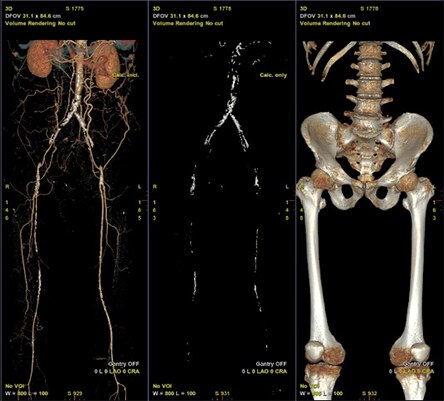

下肢血管における使用例を示す。術前CTAではAortic bifurcationからの完全閉塞となっていた(図5)。完全閉塞部分へのアプローチに対して難渋することが予測されたため、下肢血管解析結果を用いた3D Roadmap使用を検討した。AWVS7は下肢血管解析ソフトを用いることで自動的に血管、骨(術中3D Roadmapの位置合わせ用)を作成する(図6)。狭窄症例などでは自動作成された血管3Dを透視と重ねる3D Roadmapが治療サポートになるが、CTO症例ではワイヤーを進めるためのラインの有用性に着目し、CTO部分を含めた血管センターラインを作成した(図7)。血管センターラインはワイヤーを進める際のReferenceとして有用(図8)であり、3次元での位置情報を有したラインであるため、角度変更やFOV変更、テーブル移動にも追従する。また治療前のDSAでは表示されないTrue面を表示させることは、手技を進めていく中で有用なサポートになったと当院医師よりフィードバックがあった。3D Roadmapは術中にボリュームレンダリングの透過度変更や表示の有無、センターラインの表示の有無も変更可能である。CTO部分を通過させている場合にはセンターラインの表示、通過後のバルーン拡張やステント留置時にセンターラインではなく、ボリュームレンダリング表示による病変部の逆描出など場面に合わせた変更を可能としている。また任意5倍までのデジタルズーム表示機能もあり、今後の症例で使っていきたい。

図6 自動生成された術前CTAの血管、石灰化、骨のVolume

図7 CTO部分を含めた血管解析によるセンターラインとLumen View表示

図8 術中での3D Roadmap(左図は血管Volume、右図は石灰化Volumeをfusion)

完全閉塞部分を含めた血管センターライン:緑色